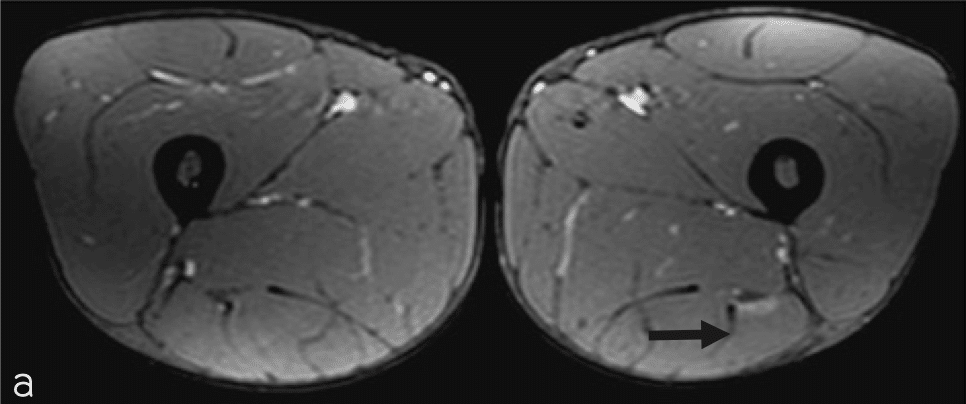

・Ⅱ型1度

(奥脇 透:大腿二頭筋肉ばなれの MRI 分類、臨床スポーツ、2019より引用)